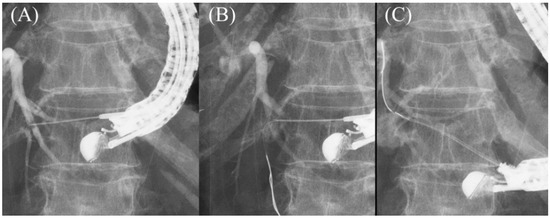

- Paik, W.H.; Park, D.H.; Choi, J.H.; Choi, J.H.; Lee, S.S.; Seo, D.W.; Lee, S.K.; Kim, M.H.; Lee, J.B. Simplified fistula dilation technique and modified stent deployment maneuver for EUS-guided hepaticogastrostomy. World J. Gastroenterol. 2014, 20, 5051–5059. [Google Scholar] [CrossRef]